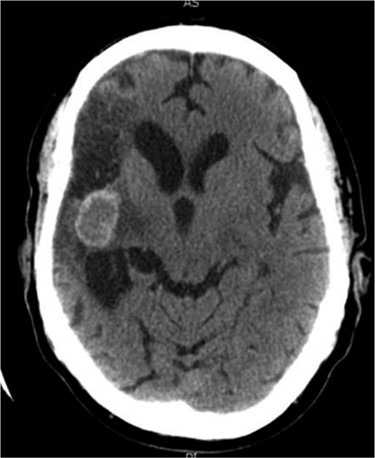

Between 2005 and 2012, the clinical condition remained stable and there were no significant radiological changes identified (Fig. 2). In July 2012, the patient re-presented with worsening left sided weakness and a left sided homonymous hemianopia. CT scan at this time demonstrated a 4 × 4cm well-defined mass of CSF density in addition to the pre-existing lesion in the right external capsule. Neither enhanced with contrast and there was no significant midline shift. An MRI head showed the lesion to contain a significant solid component. It appeared somewhat vascular and there was suspicion that it could represent a low-grade tumour (Fig. 3). The patient underwent a right-sided craniotomy to remove the mass.

Axial MRI head (2012) demonstrating 4 × 4 cm solid mass with surrounding fluid enhancement.